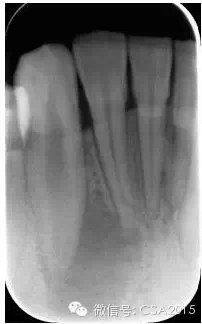

1 術(shù)前拍攝X線片評(píng)估牙齒冠、根情況以及牙槽骨情況

在根管治療過程中,在根管治療術(shù)前拍X線片,以幫助診斷,了解髓室的位置和根管數(shù)目及形態(tài),測(cè)量根管工作長(zhǎng)度及日后隨訪和評(píng)價(jià)療效提供對(duì)比的依據(jù)。